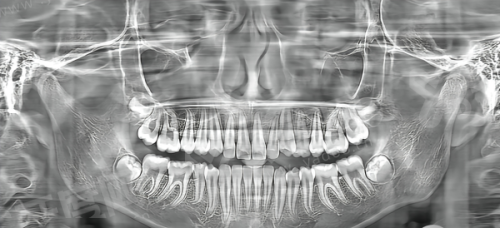

1、特别多怕看牙的朋友一想到取模要咬那种硬邦邦的石膏就头疼,甚至容易引发恶心干呕。沈阳国睿口腔直接引进了口内扫描仪,只需要拿着小探头在嘴里转一圈,几分钟就能生成高精度的三维牙齿模型。

2、这种技术不仅让患者舒服多了,更重要的是数据极其精细。医生能直接在电脑上模拟牙齿移动的全过程,连每一颗牙旋转的角度都能算得清清楚楚,避免了传统取模可能出现的变形误差。

3、对于复杂病例,比如骨性凸嘴或者深覆合,这种数字化模型能让医生提前预判风险,制定出更稳妥的矫治方案,让矫正过程少走弯路。